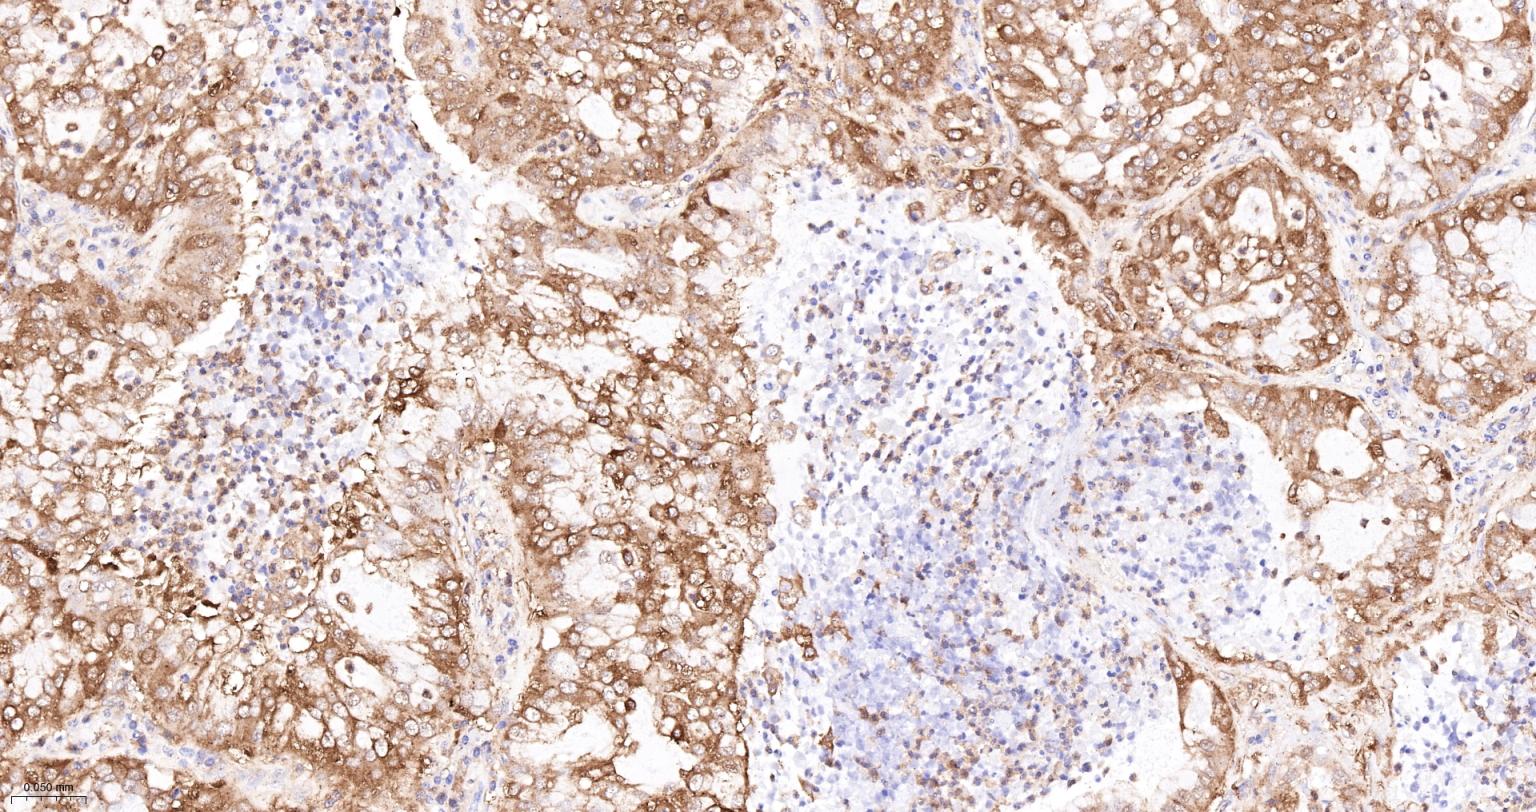

Paraformaldehyde-fixed, paraffin embedded Human Cervical Cancer; Antigen retrieval by boiling in sodium citrate buffer (pH6.0) for 15 min; Antibody incubation with PKM2 Monoclonal Antibody, Unconjugated(bsm-61301R) at 1:200 overnight at 4°C, followed by conjugation to the SP Kit(Rabbit, SP-0023) and DAB (C-0010) staining.